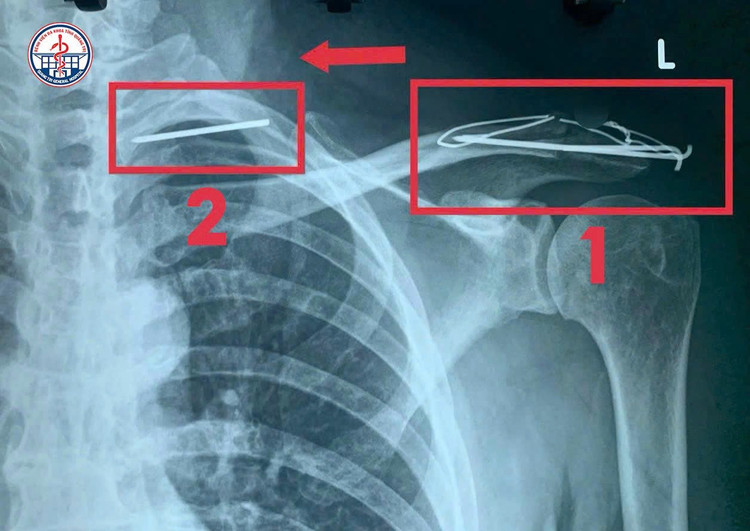

Dụng cụ kết hợp xương đã xuyên thành ngực vào đỉnh phổi - Ảnh BVCC

Kết quả chụp CT ngực khiến các bác sĩ không khỏi bất ngờ: Một dị vật kim loại đã xuyên qua thành ngực, đi vào thuỳ đỉnh phổi trái và tiến sát vùng cột sống cổ. Dị vật có nguy cơ tiếp tục di chuyển vào trung thất, gây tổn thương các cơ quan quan trọng như tim, phổi, mạch máu lớn – nguy cơ đe dọa tính mạng.

Hình ảnh dụng cụ di chuyển trong phổi - Ảnh BVCC

Khai thác bệnh sử, bệnh nhân cho biết đã từng phẫu thuật cố định trật khớp cùng - đòn bằng đinh Kirschner cách đây 3 năm.

Tuy nhiên, sau mổ bệnh nhân không tái khám và không tháo đinh đúng thời điểm như chỉ định (6–12 tháng). Hậu quả, đinh Kirschner bị gãy mỏi, rồi di chuyển vào bên trong lồng ngực.